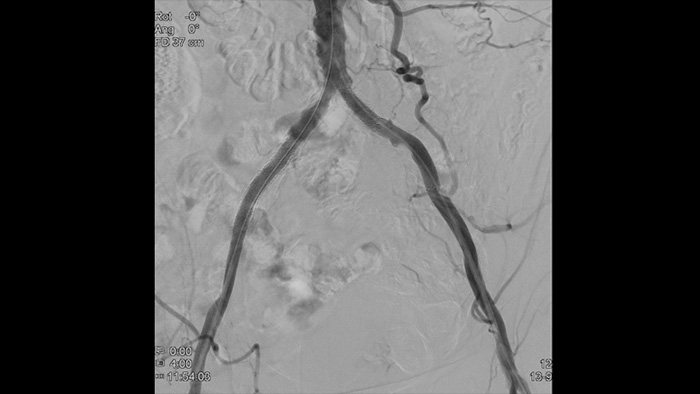

Imágenes de alta definición de vasos con un detalle vascular superior para facilitar estrategias de tratamiento, navegación y seguimiento precisos.